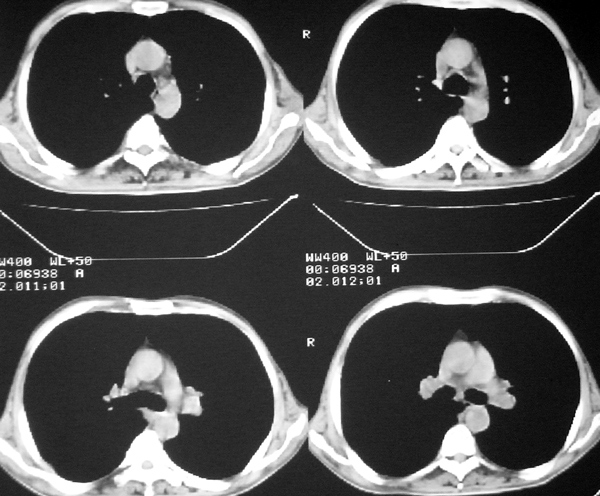

右肺囊实性占位 患者拒绝穿刺活检  近期始终间断性发高烧 使用消炎控制, 左鼻翼部有多发皮肤溃疡

双肺呈毛玻璃状,胸膜旁有多个小囊状气腔。右下囊实性病灶内有园形气体影,边缘光滑,与之相连的胸膜稍增厚,间断发热,抗炎效果不好。考虑机会性感染可能性大。

右下肺占位性病变,其边缘较光整无明显分叶,似有包膜,邻近胸膜无凹陷征及牵拉征象,包块内见数个大小不等气液面及不规则透亮影,纵隔未见明显淋巴结肿大。结合上次ct检查,考虑:炎性包块或真菌感染包块可能性大,周围型肺癌可能性小。

考虑右肺下叶慢性肺脓肿;不排除周围型肺癌。